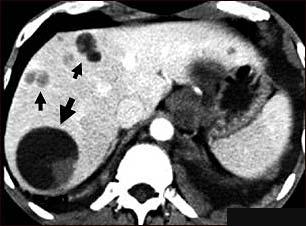

Boala hidatica – Echinococcoza sau hidatidoza